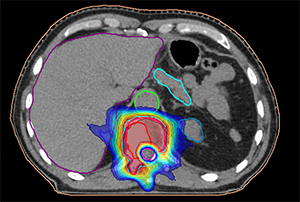

Планирование СЛТ при опухоли позвонка.Стереотаксическая радиохирургия и стерео-таксическая лучевая терапия (СЛТ) — методы, обеспечивающие подведение очень высокой дозы за один или несколько сеансов с субмиллиметровой точностью. Только за 2024 год в МГКОЦ лечение по данной технологии получили более 100 пациентов. В мировой практике известны системы «Кибер-нож» и «Гамма-нож», последняя успешно применяется в РНПЦ онкологии и медрадиологии им. Н. Н. Александрова.